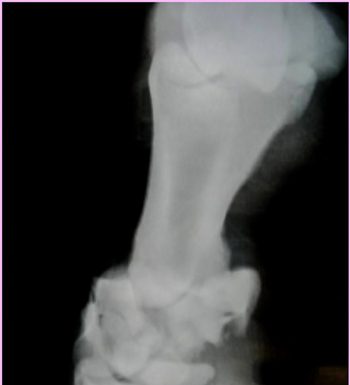

Horses love to run, plain and simple. And, we ask them to do athletic exercises that put maximal load on their limbs. Long bone fractures typically occur with a misstep or trauma due to impact from a kick, collision,...